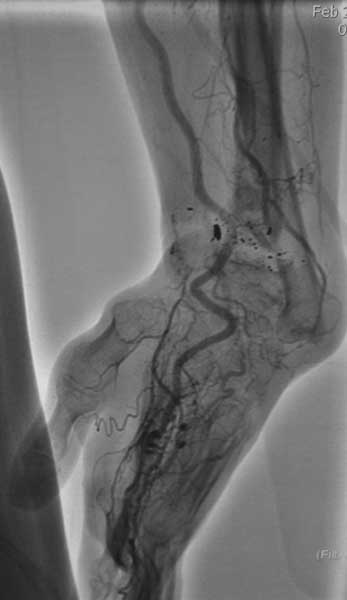

[Ortho] Посттравматический дефект в области метаэпифиза лучевой кости слева.

Вот дополнительные снимки